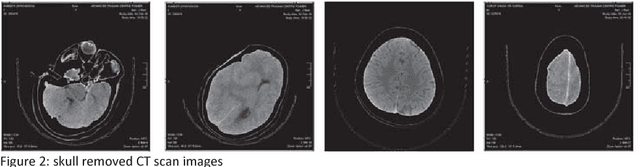

Abstract:Computed tomography imaging is well accepted for its imaging speed, image contrast & resolution and cost. Thus it has wide use in detection and diagnosis of brain diseases. But unfortunately reported works on CT segmentation is not very significant. In this paper, a robust automatic segmentation system is presented which is capable of segment complete brain matter from CT slices, without any lose in information. The proposed method is simple, fast, accurate and completely automatic. It can handle multislice CT scan in single run. From a given multislice CT dataset, one slice is selected automatically to form masks for segmentation. Two types of masks are created to handle nasal slices in a better way. Masks are created from selected reference slice using automatic seed point selection and region growing technique. One mask is designed for brain matter and another includes the skull of the reference slice. This second mask is used as global reference mask for all slices whereas the brain matter mask is implemented on only adjacent slices and continuously modified for better segmentation. Slices in given dataset are divided into two batches, before reference slice and after reference slice. Each batch segmented separately. Successive propagation of brain matter mask has demonstrated very high potential in reported segmentation. Presented result shows highest sensitivity and more than 96% accuracy in all cases. Resulted segmented images can be used for any brain disease diagnosis or further image analysis.